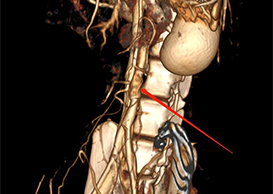

CT检测结果

REVOVAS®植入恒河猴后1670天, 完全再生的血管组织保持长期通畅。